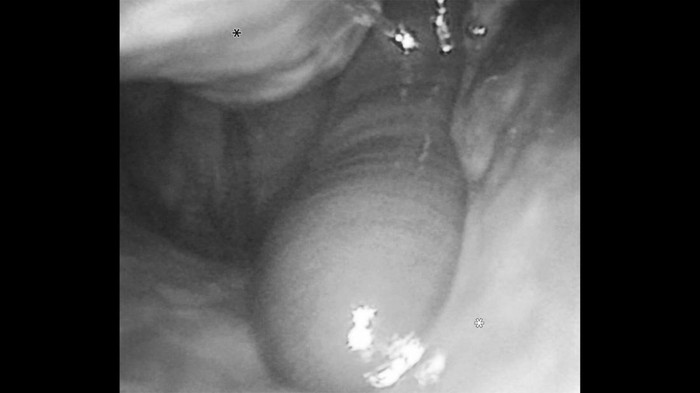

Kasus langka ini dilaporkan oleh dokter di First Hospital of Hunan University of Chinese Medicine dan dipublikasikan dalam New England Journal of Medicine. Dalam laporan tersebut, dokter juga menyertakan foto kondisi lintah yang ditemukan di rongga hidung pasien.

Saat dilakukan endoskopi, dokter menemukan penyebab yang tidak biasa. Seekor lintah yang masih hidup dan menggeliat, berusaha menghindari cahaya alat pemeriksaan.